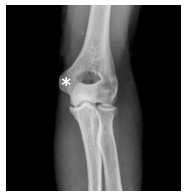

Na radiografia da região do cotovelo apresentada a seguir, a estrutura marcada corresponde: